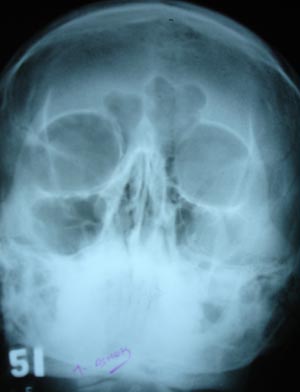

Sinusitis